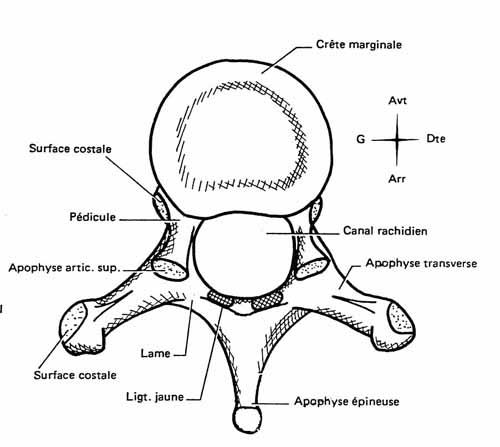

Tu peux analyser les lames sur le cliché de profil pour le rachis cervical, dorsal et lombaire ainsi que sur l’incidence de ¾ de lombaire où tu déroules les chiens de la chapelle

Les pédicules tu les analyses en coupe optique sur les incidences de face et sur le profil

Rachis cervical:  Rachis dorsal: Rachis dorsal:  Rachis lombaire: Rachis lombaire:   1. Processus articulaire supérieur 2. Pédicule droit 3. Processus transverse droit 4. Isthme 5. Processus articulaire inférieur 6. Lame opposée 7. Processus transverse opposé 8. Epineuse 9. Interligne articulaire postérieure 10. Processus articulaire inférieur opposé 11. Processus articulaire supérieur opposé Pour ce qui est de la radioanatomie; nous te laissons le soin d'apprendre tout cela grâce aux livres à ta disposition et à tes stages surtout!  Nous avions commencé une liste de livres de radiologie; à toi de t'en servir et bonnes recherches! Si tu souhaites trouver d'autres correspondances, si quelques détails t'interpellent n'hésite pas à poser des questions précises! Bon courage la marmotte!